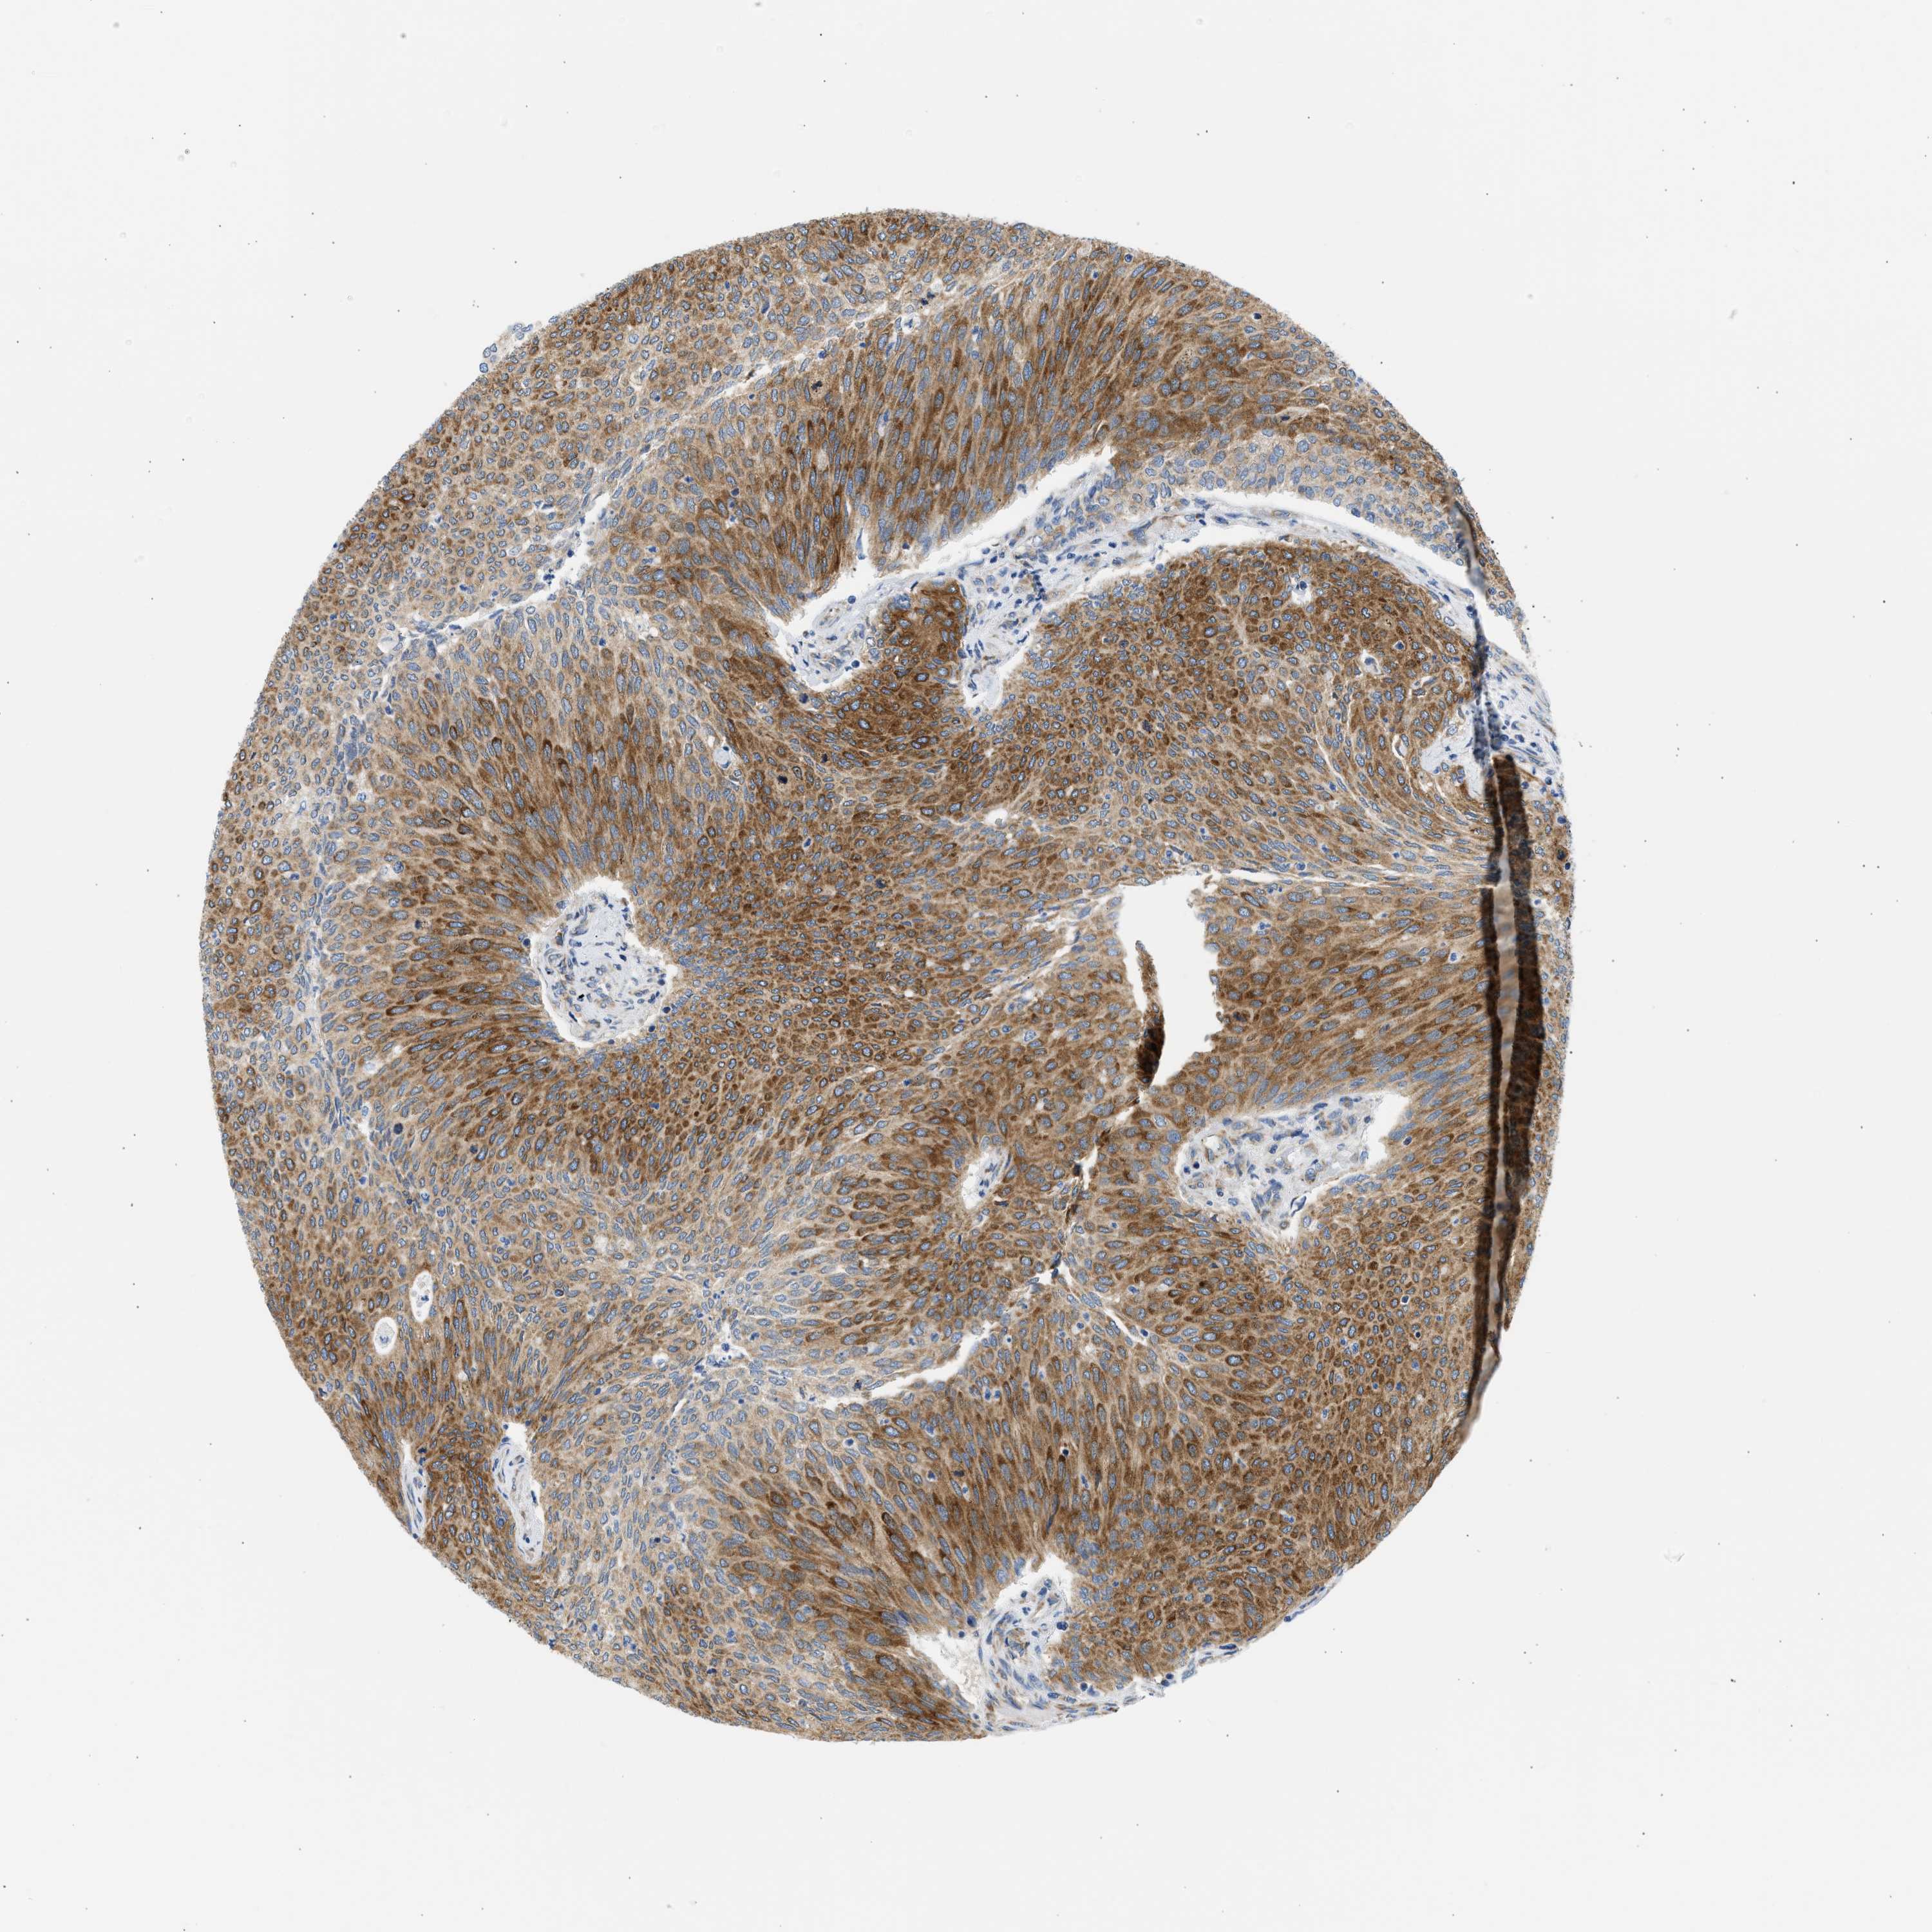

UROTHELIAL CANCER - Protein expressioni

A mouse-over function shows sample information and annotation data. Click on an image to view it in a full screen mode. Samples can be filtered based on level of antibody staining by selecting one or several of the following categories: high, medium, low and not detected. The assay and annotation is described here.

Antibody stainingi

Antibody staining in the annotated cell types in the current human tissue is reported as not detected, low, medium, or high, based on conventional immunohistochemistry profiling in selected tissues. This score is based on the combination of the staining intensity and fraction of stained cells.

Each image is clickable and will lead to virtual microscopy that enables deeper exploration of all samples and also displays staining intensity scores, fraction scores and subcellular localization as well as patient and tissue information for each sample.

Antibody HPA017389

Antibody HPA063713

Staining

High

Medium

Low

Not detected

Intensity

Strong

Moderate

Weak

Negative

Quantity

>75%

75%-25%

<25%

None

Location

Nuclear

Cytoplasmic/membranous

Cytoplasmic/membranous,nuclear

Urothelial carcinoma, Low grade

Urothelial carcinoma, High grade

Urothelial carcinoma, NOS